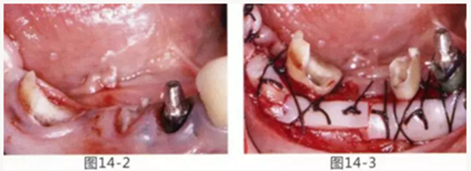

4.png

圖14-2,3 徹底去除齲壞后,試圖通過游離齦移植獲取生物學寬度和附著齦。